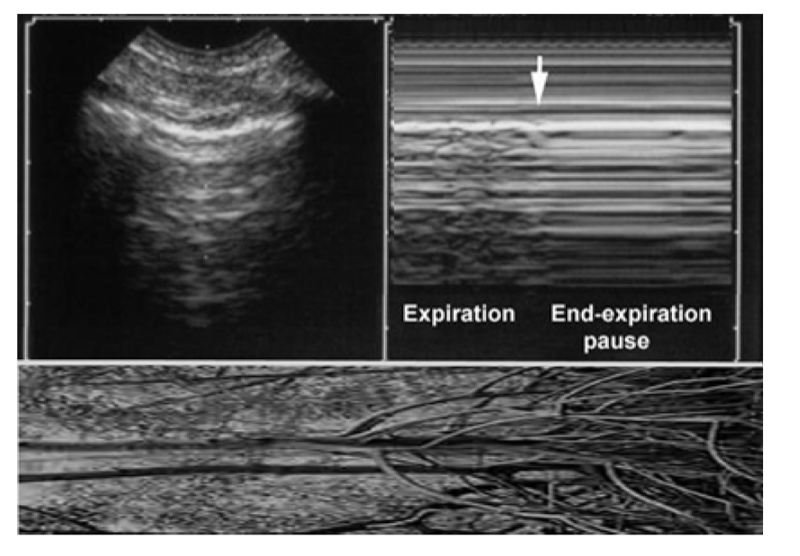

9. VARIANT 1: THE MANGROVE VARIANT

Fig. 6 The mangrove variant. Left, real-time showing a pleural line with A-lines (example here of ill-defined A-lines). Right, M-mode showing a soft interruption of the sand yielding a regular horizontal pattern at the MM-space. This interruption is progressive. This looks like aerial roots of mangrove trees (bottom image, horizontalized). The message is: don’t press the M button if not necessary.

The respiration is not a permanent dynamic; there are pauses. These physiological end-inspiratory and end-expiratory pauses are enhanced in sedated patients. These pauses generate a brief interruption (therefore, usually not seen in polypneic patients). On real-time, the lung sliding quietly stops. On M-mode, the sandy pattern of lung sliding is transiently replaced by a regular horizontal pattern evoking a “stratosphere sign” (this makes a didactic challenge, since this pattern, evoking pneumothorax. This pattern, called mangrove variant (Anecdotal note 3 ), may be confused by young users with a lung point, i.e., a main sign of pneumothorax. We must devote some lines for smashing this problem to smithereens.

1. First, the mangrove variant is a progressive phenomenon. Lung sliding is detected on real-time. It quietly comes, stops, goes, stops, comes, etc. It does not suddenly disappear (like the lung point in pneumothorax). If beginning with the real-time, there is no trouble. The mangrove variant is built by the use of M-mode. M-mode should not be used for confirming a lung sliding which has already been detected using the real-time. This is one perverse effect of an immoderate use of the M-mode.

2. Second, the lung point should be sought for only if pneumothorax is suspected, i.e., in the case of anterior absence of lung sliding associated with exclusive A-lines. The mangrove variant occurs at the entire lung surface, including the anterior parasternal areas. In other words, the only confusion should be, if any, with a limited, parasternal, clinically insignificant pneumothorax. The visualization, more laterally and on the whole lung surface, of the strictly identical pattern avoids any confusion.